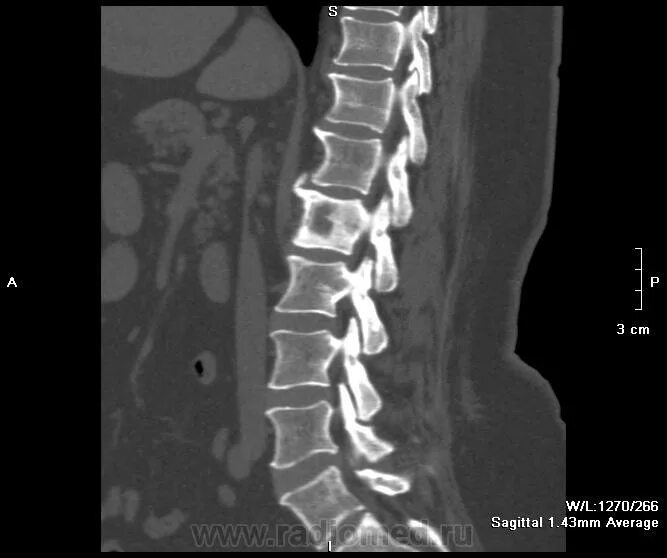

Киста в грудном отделе позвоночника